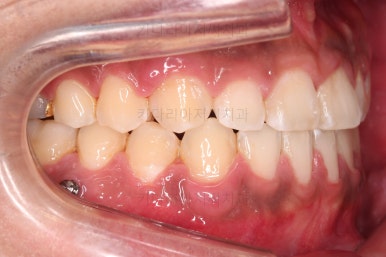

초진 시 입안의 모습입니다.

비교적 고른 편이긴 하나 아랫니가 전반적으로 밀려 나오면서 앞니끼리 부딪혀 있는 양상이고요.

어금니 맞물림도 긴밀하게 톱니바퀴처럼 위아래가 맞물려 있는게 아니라 엉성한 모습이죠.

앵글씨 3급 부정교합이라고 하는데요.